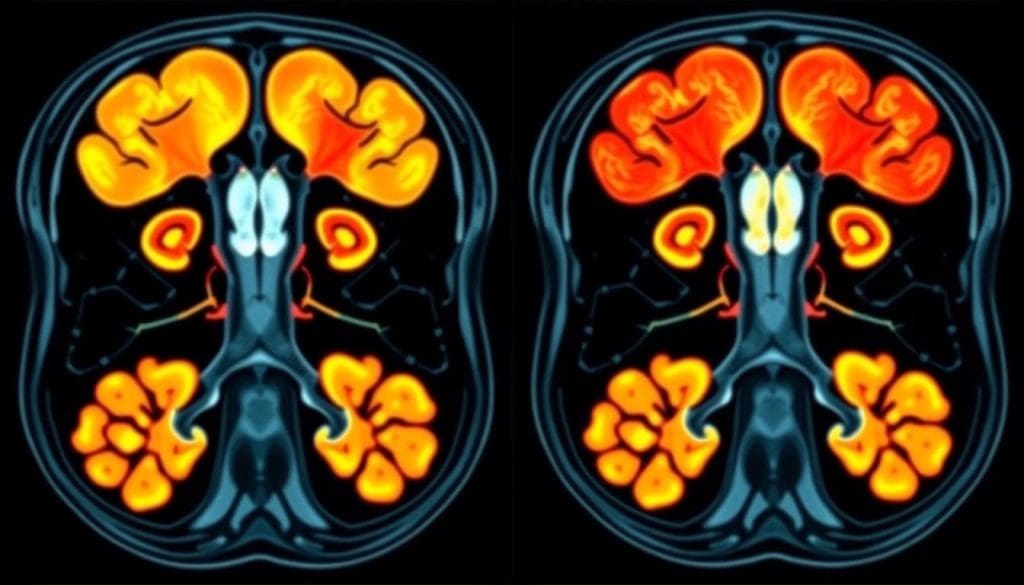

PET/CT Combination: Enhanced Diagnostic Capabilities for Lymphoma

The use of PET and CT scans together has changed how we diagnose lymphoma. This method combines the detailed images from CT scans with the metabolic activity from PET scans. It gives a clearer and more accurate view of lymphoma.

How Anatomical and Metabolic Imaging Work Together

The PET/CT combo helps pinpoint where metabolic activity is happening. It mixes the functional data from PET scans with the detailed images from CT scans. This way, doctors can spot and understand lymphoma lesions better. It’s great for finding lymphoma in tricky spots.

Latest-Generation Scanner Accuracy Rates

New PET/CT scanners are making lymphoma diagnosis more accurate. These scanners are more sensitive and specific, cutting down on mistakes. They also scan faster and are more comfortable for patients.

Key benefits of the latest-generation PET/CT scanners include:

- Improved diagnostic accuracy

- Enhanced sensitivity and specificity

- Faster scanning times

- Better patient comfort

Thanks to these upgrades, doctors can give more precise diagnoses. They can also create better treatment plans for lymphoma patients.